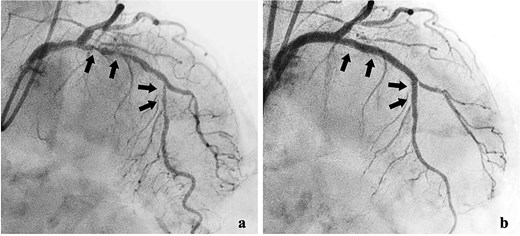

After interventional radiology, internal fixation with antegrade intramedullary nailing was performed using the blocking pin technique (Fig. 4). Tumour tissue from the fracture site was sent for pathology. The operative time was 63 min, and intraoperative blood loss (IBL) was 30 ml. She was allowed full weight-bearing depending on her condition.